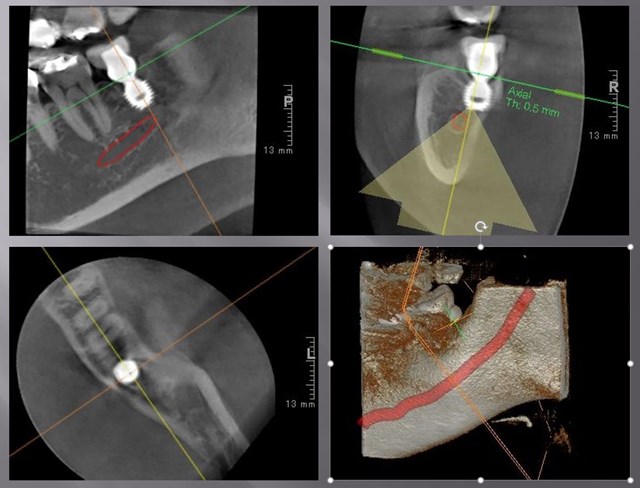

これが、仮歯の状態のCT写真です。

快適に咬めていますし、歯肉もまったく腫れていません。